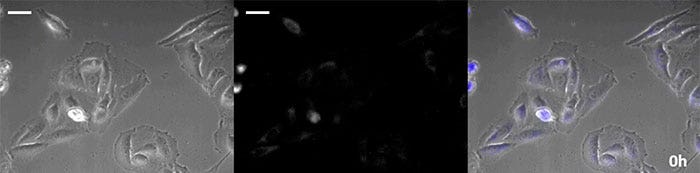

Brightfield image

Luminescence image

Overlay image

Luminescence image pseudo color (green)

Video 1. Luminescence observation of calcium ion fluctuations caused by histamine stimulation (scale bar: 500 µm)

Coelenterazine-type luciferin has especially high brightness, but, since it oxidizes in the cell within in a short time frame, timely addition is essential for long-term observation applications. To resolve this issue, we perfused the cells with high-intensity luminescent protein, while an automated substrate addition device automatically added the coelenterazine so the luminescence could be continually monitored. As a result, we succeeded in monitoring the luminescent image in combination with phase-contrast imaging for more than 24 hours (Figure 4).

0 hours

6 hours